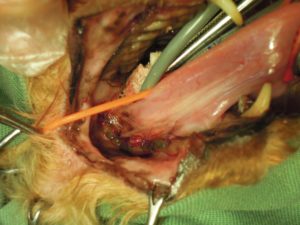

6.歯周病のため右側上顎の歯を全て抜歯し、

7.右側下顎の歯も骨折に注意して抜歯し、